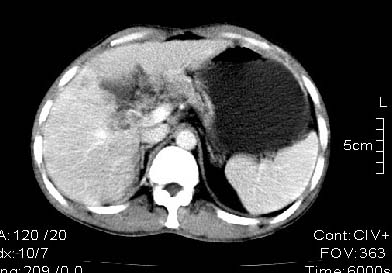

男:42岁。反复恶心呕吐半年。b超:右肝内多发占位,胆石胆囊炎.胆总管扩张

本例特点动脉期右叶近肝门区可见高密度强化,后段也见早期强化,静脉期肝门区高密度区造影剂退出,余密度均匀,考虑肝癌伴动静脉漏,肝右叶上段可见扩张胆管,考虑由于肿瘤压迫胆管引起阻塞,

鉴别 胆管细胞性肝癌,无动脉期强化,

首先我要谢谢战友给我的建议,明天我将给患者作平扫。以上为动静脉期的单幅图象资料。